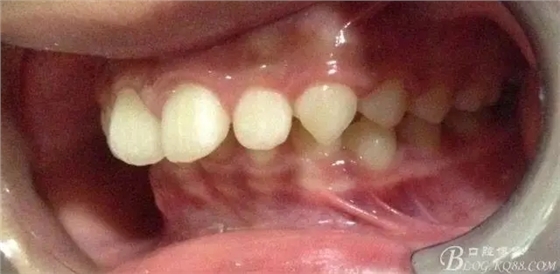

??茩z查:恒牙列,牙列式上下7-7.覆蓋二度,覆合三度,雙側磨牙關系二類,尖牙關系二類,下合3-3各牙間散在約1-1.5mm間隙,輕度唇傾,正面觀顯下頜頦部發(fā)育不足,側貌可觀察到下頜略顯后縮,上頜鼻唇角以及唇部大體正常。開口型向下,舌體正常,TMJ檢查及其它未發(fā)現(xiàn)異常。

看看口內照吧!真象“大暴牙”v假象“大暴牙”

三度深覆合,三度深覆蓋,尖牙,磨牙均二類關系!